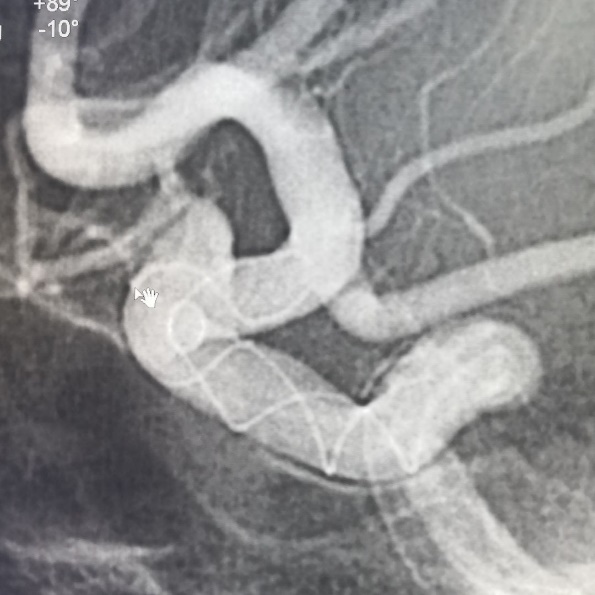

入院后行全脑血管造影证实右侧颈内动脉眼段动脉瘤。瘤颈宽约4.91mm,瘤体最大径约8.21mm,载瘤动脉远近端血管直径分别为3.07mm、3.52mm。

术前造影:

正侧位造影示动脉瘤内造影剂明显滞留,载瘤动脉通畅,血流导向作用显著。

术后即刻: